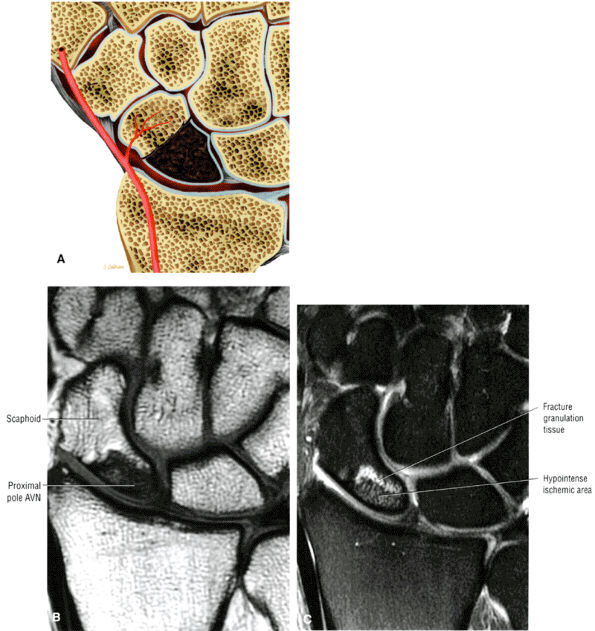

|